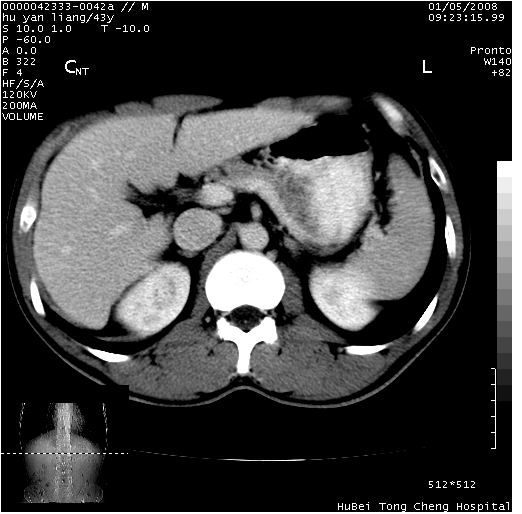

患者 男,43岁。右上腹不适1年余。既往有“肝右叶肝脓肿”病史,经保守治疗后痊愈。

b超提示:1)肝右叶肝内胆管结石。2)肝右叶占位性病变待排。

上中腹部ct轴位平扫+增强扫描(层厚10mm,螺距1.0,重建间隔10mm),图像如下:

肝右叶后段团块状钙化灶,结合病史考虑肝脓肿痊愈后表现。